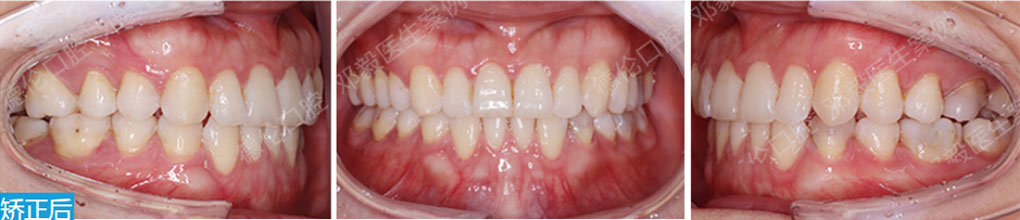

2019隱形正畸新技術耀世發布會

德倫口腔攜手全球知名隱形矯治器品牌——時代天使舉辦“時代天使新矯治技術耀世發布會”,成立矯正診室并啟動“微笑基金”,德倫口腔成為時代天使廣東官方指定醫院。